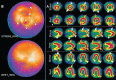

Herein, we report the case of a 56-year-old male patient with acute myeloid leukemia (AML) in remission who had asymptomatic myocardial ischemia on myocardial perfusion imaging and transthoracic echocardiography. Angiography did not reveal any significant coronary artery disease. Although the etiology is not entirely clear, this case suggested that myocardial perfusion imaging should be considered in patients with AML who received idarubicin to screen for possible myocardial dysfunction.